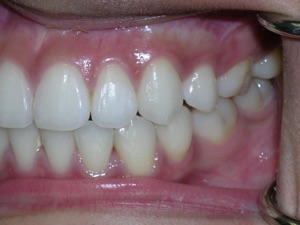

So here’s a case of an open bite, with a protrusion. There was a fair degree of crowding as well.

We decided to do porcelain brackets and have select teeth removed. Take a look.

Here are the results.